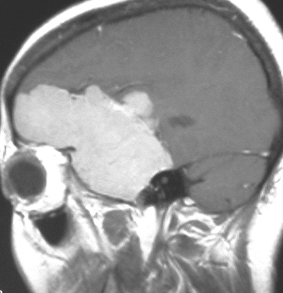

典型的な髄膜腫

この髄膜腫は中程度の大きさのものです。円蓋部髄膜種という最も多い最も手術の簡単なタイプです。麻痺や失語症やてんかんなどの症状はありません。とても美しくて若い女性の髄膜腫でしたが,子供に遺伝はしませんし,癌などと違ってタバコなどこれといった原因がなくて発生するものです。

MRIでの髄膜腫の見え方は撮影の仕方によっていろいろです。左からT1強調画像,T2強調画像,フレア画像といいます。腫瘍の横に小さく白い領域がありますが,これは脳の腫れた部分で脳浮腫といいます。髄膜腫があると周囲に脳浮腫が生じることがあります。

最も見やすいのが,ガドリニウム造影剤を注射して撮影するものです。一般的に髄膜腫は造影剤で白く映し出されます。この腫瘍は左脳側にあります。MRIの軸面という輪切りの写真では左右が逆になりますから注意してください。脳を下から見た図になっています。MRIはいろいろな方向から腫瘍を見ることができますが,右は冠状断という正面から見た図です。よく見ると腫瘍の上と下のはじっこに線状に糸を引いたように造影される部分があります。これをテールサイン(しっぽのサイン)といいます。腫瘍が硬膜に沿って延びている可能性があることを示しています。